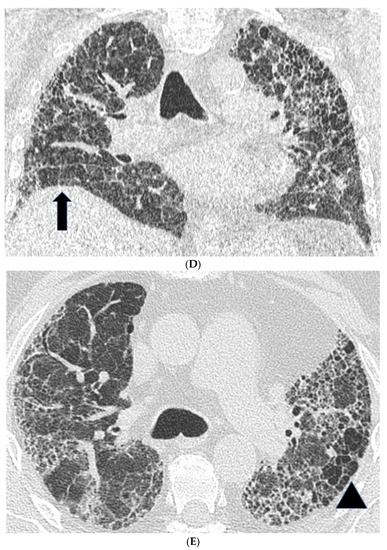

Figure 1. Features suggestive of chronic hypersensitivity pneumonitis in different patients. (A) Spared pulmonary lobules are visible within non-fibrotic lung bilaterally (arrows); background fibrosis is evidenced by peripheral reticulation and traction bronchiectasis (black arrowheads). (B,C) A predilection towards bronchocentricity of the fibrosis in the upper lobes is evident on axial (arrowheads) and coronal (arrows) images. (D) An upper and midzone predominance to the fibrosis, characterised by reticulation and traction bronchiectasis, is seen on a coronal CT. Incidentally, volume loss in the right lung is noticeable by slight tenting and elevation of the right hemidiaphragm (arrow). (E) A UIP pattern with honeycomb cysts is visible in the left midzone of the lung (arrowhead) in a 74-year-old male ex-smoker. A surgical biopsy performed a few years before this CT had demonstrated findings compatible with fibrotic hypersensitivity pneumonitis.

In fibrotic HP, CT patterns including reticulation, traction bronchiectasis and volume loss, with or without evidence of honeycombing, are all seen (Figure 1) [26,28]. Patients often demonstrate an upper lobe predominant distribution of fibrosis, but diffuse and lower lobe predominant changes have also been described. Furthermore, a faint bronchocentricity to the fibrosis can be observed at the lung apices. Similarly, reticulation in fibrotic HP is considered to have a predominantly subpleural or peri-bronchovascular distribution.

Mosaic attenuation with patchy areas of air trapping in a lobular distribution, more obvious on expiratory scans, is another important CT feature in HP. Lobular air trapping represents indirect evidence of small airways obstruction. (Figure 1A) However, mosaic attenuation can also be observed in other fibrotic lung diseases, including fibrotic sarcoidosis and connective tissue disease associated interstitial lung disease, also related to small airways involvement. As a result, lobular air trapping, which is often considered characteristic, may be a relatively non-specific finding. Interlobular septal thickening can be particularly profuse in fibrotic HP, although this is also a feature of fibrotic sarcoidosis. Consolidation is rare in HP and should raise the suspicion of alternative diagnoses such as fibrosing organizing pneumonia or sarcoidosis. Finally, cysts have been reported in 13% of patients with subacute HP but can also be seen in fibrotic HP [29]. The cysts are suspected to be a result of bronchiolar obstruction secondary to peribronchiolar lymphocytic inflammation, similar to that seen in lymphoid interstitial pneumonia.